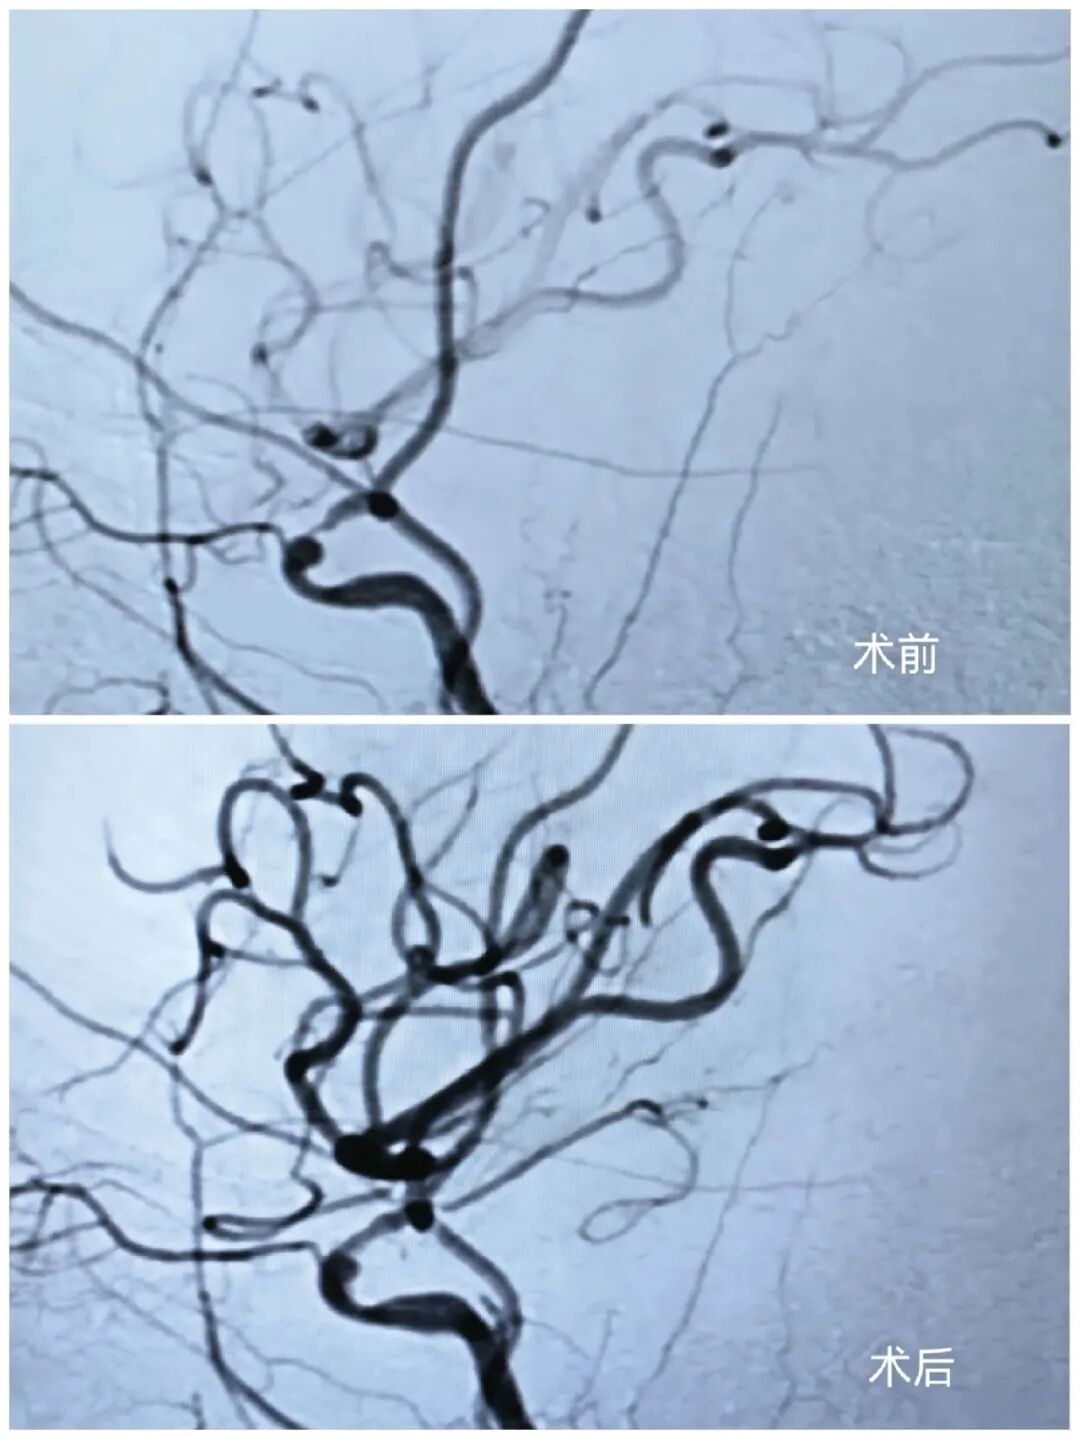

手术由江泓主任医师主刀,张欧医生及吴瀚博医生担任助手。术中,团队凭借精湛技术,成功对两处串联性重度狭窄实施精准球囊扩张,并在高难度血管条件下,顺利置入一枚血流导向装置及一枚辅助支架。

术后即刻造影显示,刘女士远端血管血流恢复通畅,提示缺血风险得到有效解除;同时,动脉瘤内可见明显造影剂滞留,提示动脉瘤已被成功隔绝,出血风险明显下降。手术获得圆满成功。